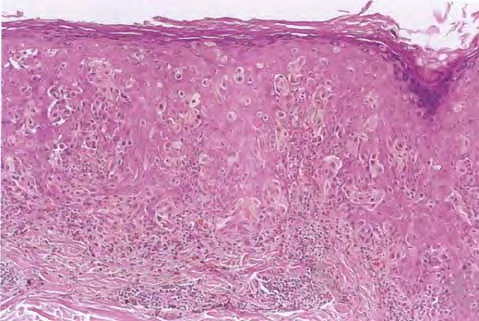

Architectural pattern features of importance in the diagnosis include the large diameter of the lesions, poor circumscription (the last cells at the edge of the lesion tending to be small, single, and scattered), and asymmetry (one half of the lesion does not mirror the other half) . The epidermis is irregularly thickened and thinned, in contrast to the uniformly elongated rete ridge pattern of a dysplastic nevus . Rather uniformly rounded, large melanocytes are scattered in a pagetoid pattern throughout the epidermis. The large cells lie predominantly in nests in the lower epidermis and singly in the upper epidermis. The nests tend to vary a good deal in size and shape and to become confluent. Dermal melanophages and a dermal infiltrate are regularly present. The lymphocytic infiltrate may be patchy and perivascular as in a dysplastic nevus but is typically dense and bandlike, especially in invasive lesions.

Cytologically, the lesional cells are rather uniform and have abundant cytoplasm containing varying amounts of melanin that often consists of small, “dusty” granules. They are almost entirely devoid of readily visible dendrites. The nuclei tend to be large and hyperchromatic, with irregular nuclear membranes and irregularly clumped chromatin . This uniform cytologic atypia is of considerable diagnostic importance and contrasts with the random cytologic atypia of dysplastic nevi.

When the lesion is in situ, the basement membrane is intact  and there are no lesional cells in the dermis. In an invasive but nontumorigenic lesion (invasive radial growth phase or microinvasive melanoma), cells similar to those in the epidermis are present in the dermis in the form of small nests, with no nests larger than those in the epidermis, and with no dermal mitoses . When tumorigenic vertical growth phase is present, there is at least one, or often more than one, cluster of cells in the dermis that is larger than the largest intraepidermal nest, and/or there may be lesional cell mitoses in the dermis .